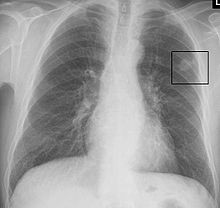

1、影像室檢查 肺癌的影像診斷中,最基本的是胸部X 線攝片,體層攝影則是胸片的補充檢查方法。但我們也得承認隨著CT、MRI 在傳統的胸部X 線診斷基礎上,對肺癌的定性、定位、分期的診斷有了很大的提高。

(1)、肺癌的X 線表現:

②周圍型肺癌:表現為密度不勻之不規則浸潤樣影,瘤體可呈平滑邊緣的無分葉球形,但多數情況下,瘤體邊緣是分葉狀的,即謂之“分葉征”。肺癌的分葉徵象出現率較高達80%,故對其鑑別診斷有一定意義。瘤體陰影的邊緣在X 線片上常較模糊而不銳利,典型者為細短狀毛刺影。如發生癌性空洞,形態可分為厚壁空洞、薄壁空洞和多發小空洞。空洞壁的各部分厚薄不勻,內壁不整,有時可見附壁結節。空洞多見於鱗癌。